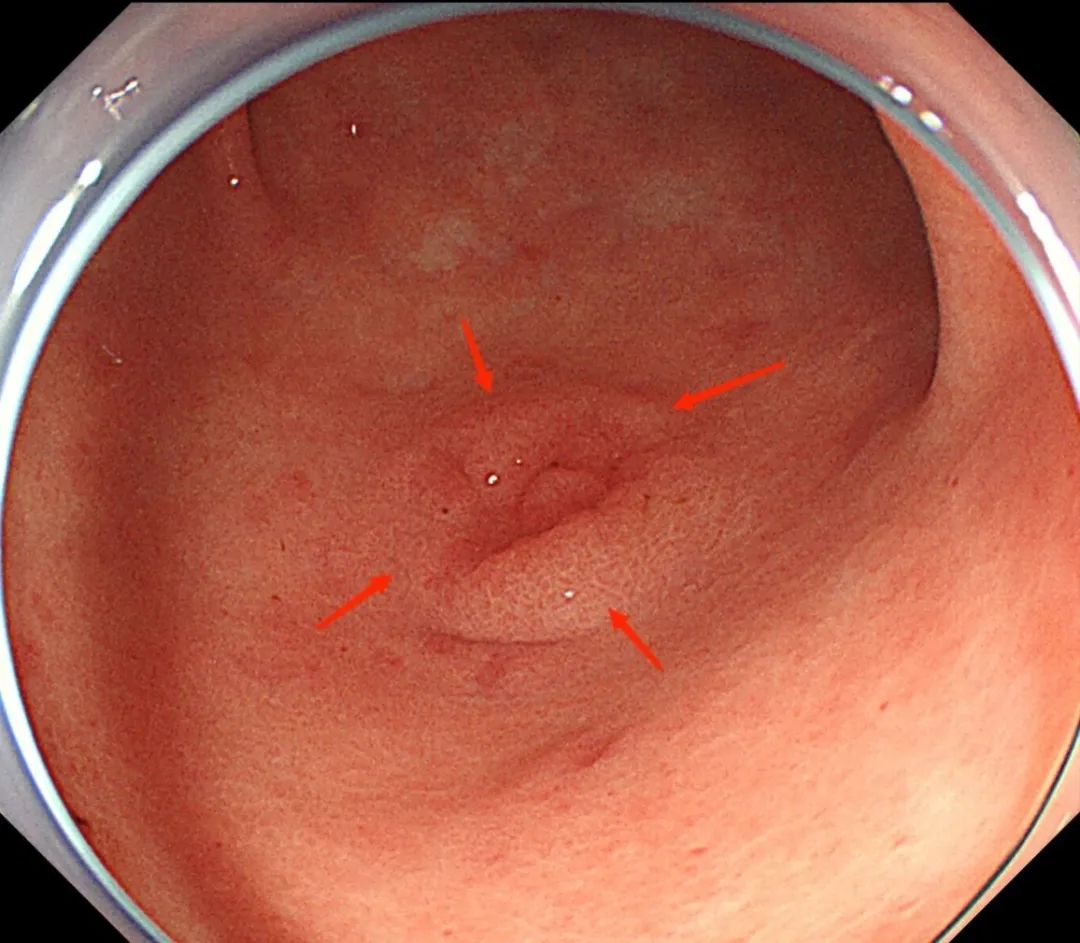

在科室何林方主任的带领下,科室常规开展无痛胃肠镜、精查染色胃肠镜、超声胃肠镜、色素放大内镜、窄带成像技术(NBI)、磁控胶囊胃镜、胶囊小肠镜等检查,能开展胰胆疾病的内镜下治疗(ERCP):包括十二指肠乳头肌切开(EST)、胆管取石术、胰胆管支架置入术、内镜下鼻胆管引流术;食管胃底静脉曲张套扎、硬化剂、组织胶注射治疗;内镜下的粘膜剥离术(ESD)、内镜黏膜下切除术(EMR)、经口内镜食管括约肌切开术(POME)、经内镜黏膜下隧道肿瘤切除术(STER)、空肠管置入术;痔硬化、套扎治疗;胃造瘘(PEG)、食管、肠道支架置入;食管狭窄扩张术,食管瘘口封堵术;经颈静脉肝内门-体分流术(TIPS)、超声内镜引导下的胃曲张静脉精准断流术(EUS-SVD)、内镜超声引导下胆道引流术(EUS-BD)、内镜下幽门括约肌切开术(G-POME)、经内镜逆行阑尾炎治疗术(ERAT)等国际最新内窥镜微创治疗。